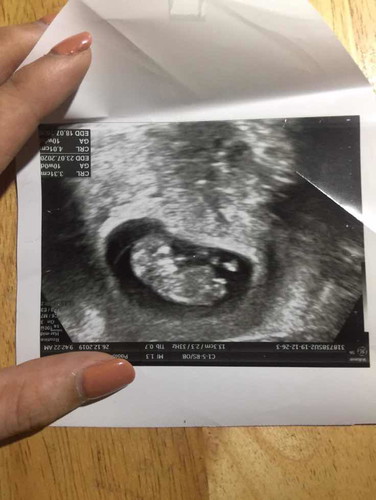

คาง

สอบถามแม่ๆหน่อยคะ นี่ใช่คางน้องไหมคะ แม่ๆคนไหนเคยซาวด์แล้วออกมาเปะในใบบ้างคะ

น่าจะน้องนอนขดตัวอยู่นะคะ อยู่ในช่วงพัฒนาแขนขาค่ะ ของเราตอนอายุครรภ์16วีคค่ะ

น่าจะส่วนคางหรือช่วงคอค่ะ

คางยาวมากค่ะ. แม่คางสั่น5555